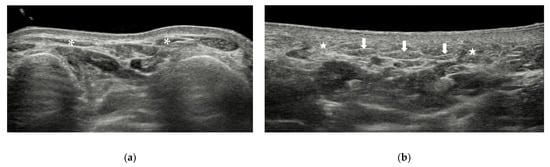

4.2.1. Synovitis and Tenosynovitis

| Synovitis | 2nd to 4th MTP joints | hypoechoic, poorly compressible, non-displaceable intra-articular tissue, with or without increased vascularity |

| Tenosynovitis | / | tendon sheath distension with surrounding effusion, “target” sign in transverse view |